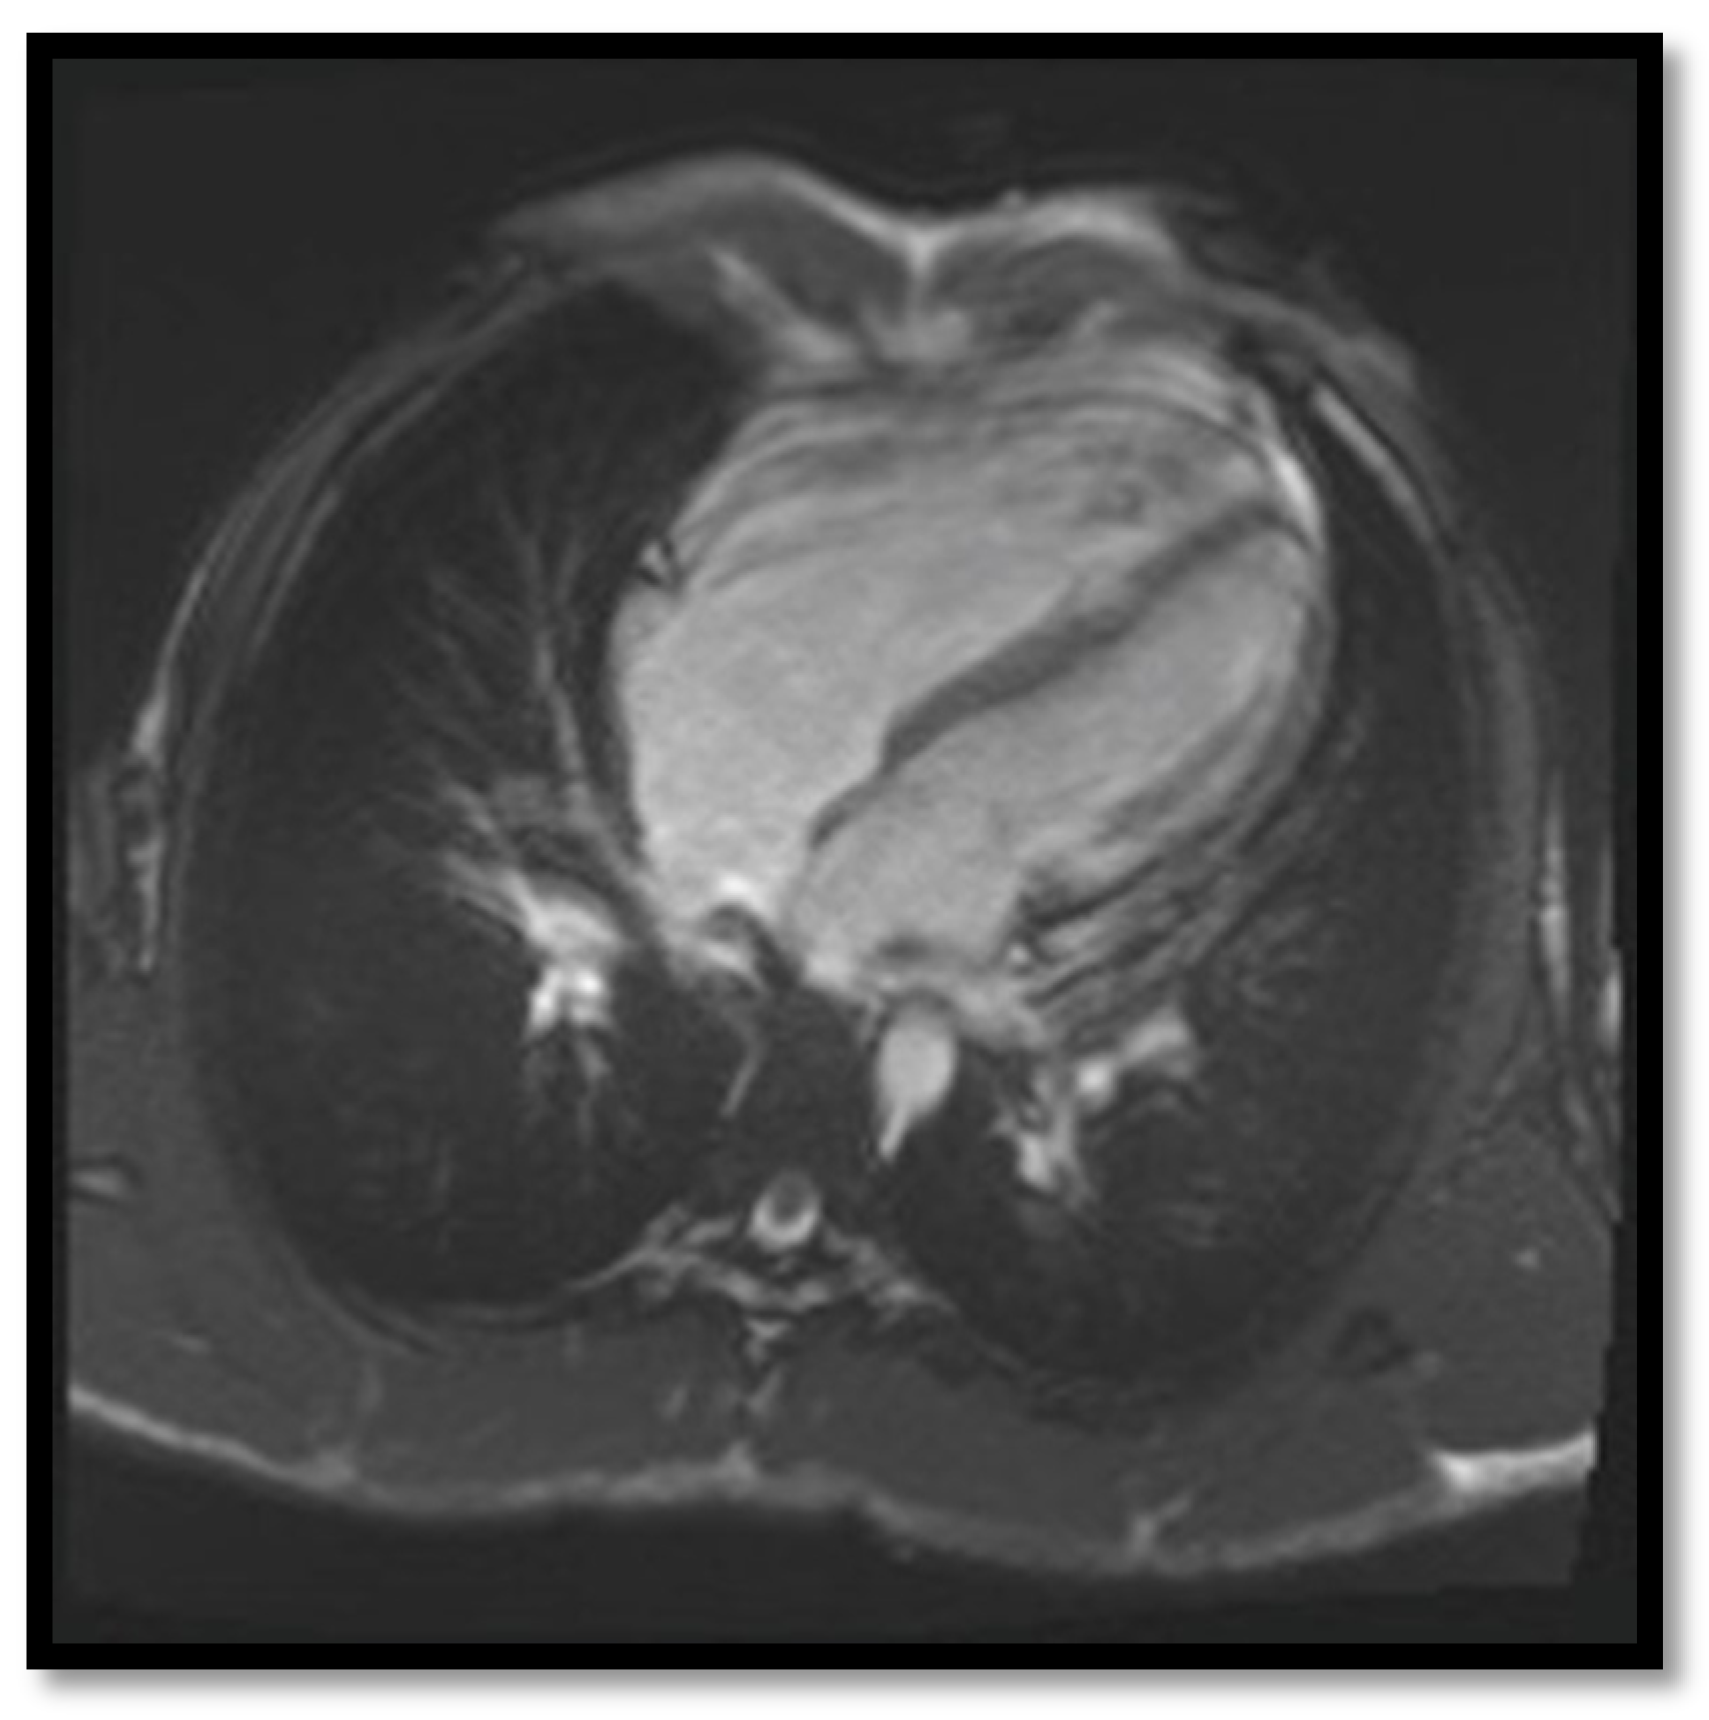

- Delayed enhancementThe significance of delayed enhancement in cardiac MRI is fibrosis, edema, or inflammation [49]. It is not possible to clearly differentiate the exact cause of the increase in the extracellular volume. The abnormal tissue causes gadolinium retention while normal myocardial tissue does not. It is estimated that approximately 67% of patients with ARVC have delayed enhancement of the ventricular walls. In the study of Tandri et al. [49], 6 out of 10 patients with ARVC presented induced VT during electrophysiological study, and 4 did not have induced VT. It is relevant to mention that among patients with inducible VT, all six had delayed enhancement in cardiac MRI, and among those who were not inducible, only one had delayed enhancement in MRI.